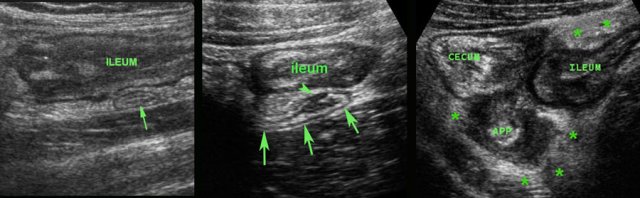

Another pitfall is when secondary wall thickening of ileum or right colon is visualized, but the underlying appendicitis is overlooked.

In this patient initially the submucosal colonic wall thickening was interpreted as infectious ileocolitis by Campylobacter or Salmonella.

Positioning of the probe in the right flank, revealed the inflamed appendix (arrow) surrounded by inflamed fat (*).

The presence of inflamed fat in itself is a key finding, because this is never found in infectious colitis.

In these two patients initially the mucosal thickening of the terminal ileum as a sole US finding was interpreted as Crohn’s ileitis or infectious ileitis.

A second US exam revealed the underlying appendicitis (arrow) causing secondary thickening of the neighboring ileum.